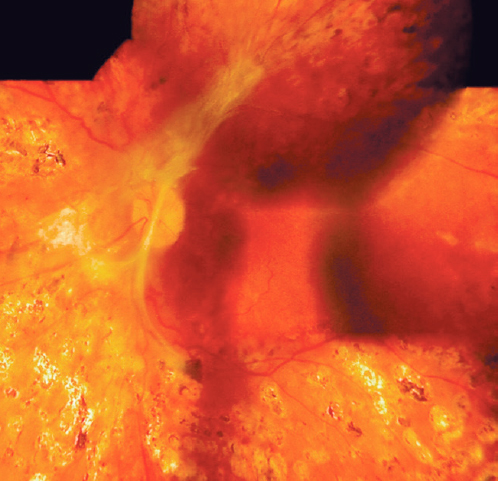

Наличие и степень тяжести ПДР оценивали по клинической классификации ETDRS (1991). Согласно данной классификации в 24 глазах имела место ПДР тяжёлой стадии. Это выражалось наличием ретинального глиоза с зонами ретинальной неоваскуляризации и пролиферации, локализующимися, преимущественно, по ходу сосудистых аркад. Из них на 12 глазах глиоз и перипапиллярная неоваскуляризация распространялись на диск зрительного нерва (ДЗН), на 9 глазах — захватывали ДЗН и сосудистые аркады; на 3 глазах — распространялись от ДЗН и сосудистых аркад на межаркадные промежутки (рис. 1).

Рис. 1. Пациент А, 28 лет. Левый глаз. Глиоз на диске зрительного нерва, аркадах, тракционная отслойка сетчатки, гемофтальм. Сахарный диабет 1-го типа в течение 19 лет. HbA1C 8,5%.